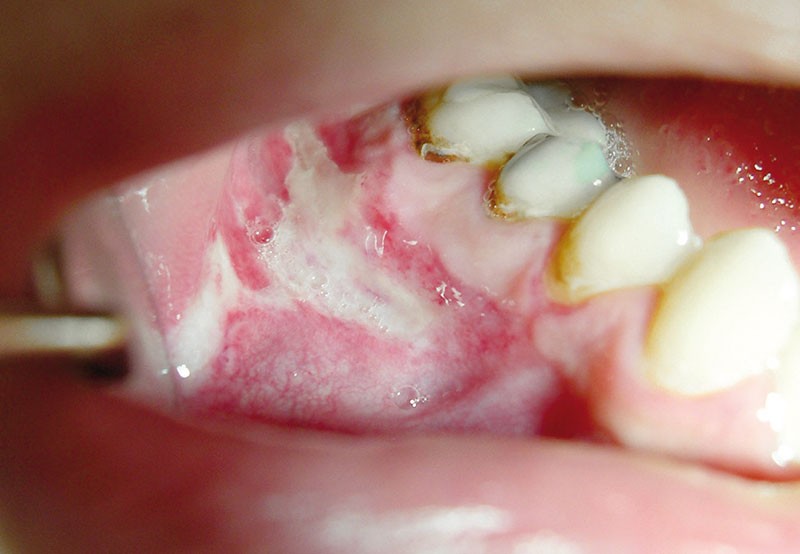

Les ulcérations orales traumatiques sont d’un diagnostic aisé. Elles sont le plus souvent uniques et guérissent après suppression de la cause en 8 à 15 jours. A l’inverse les ulcérations orales iatrogènes d’origine médicamenteuse sont de diagnostic plus difficile car volontiers multiples et pouvant se manifester à distance de l’introduction du médicament. Leur diagnostic repose sur un faisceau d’arguments, intégrant des donnés chronologiques, des données sémiologiques et sur la connaissance des médicaments les plus souvent rapportés comme inducteurs d’ulcérations orales.

Après l’aphte, les ulcérations les plus fréquentes sont de causes traumatiques ou iatrogènes. Elles sont à rechercher au cours de la démarche diagnostique. L’anamnèse prend ici tout son sens en permettant au praticien de recueillir tous les éléments nécessaires à l’établissement du diagnostic dont l’histoire de la maladie : début d’apparition, événement particulier en relation avec le déclenchement de la lésion, symptomatologie, mode d’évolution, chronicité de la lésion… L’examen clinique doit être minutieux et complet. Il débutera par un examen exobuccal à la recherche d’adénopathies et de tuméfactions. Il se poursuivra par un examen minutieux de l’ensemble de la cavité orale (muqueuses et dents) ainsi que des éventuels éléments prothétiques.

Ulcérations traumatiques

« Le trauma est une blessure locale produit par un agent extérieur » [1]. Il peut être généré par un agent physique, chimique ou thermique.

Ulcérations traumatiques induites par un agent physique